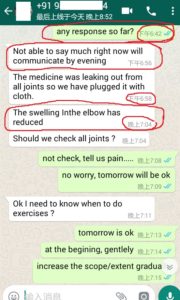

1. The Gentleman in Kenya started his treatment at his home April 27, now he said: (will update his more progresses soon)